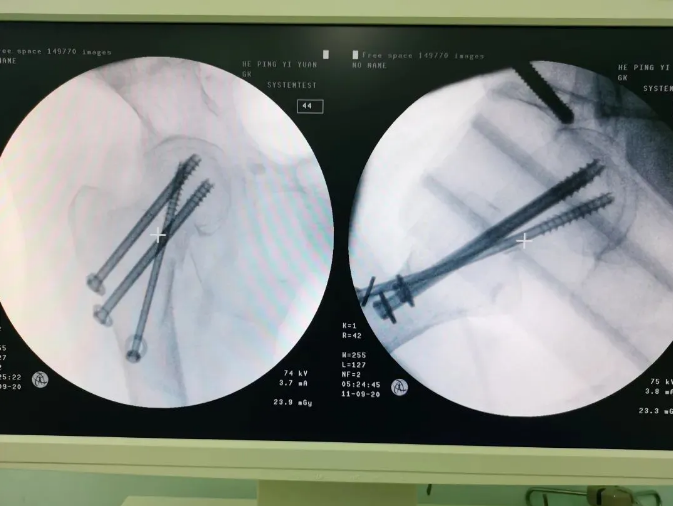

天璣機(jī)器人置入螺釘

螺釘置入后

天璣?骨科手術(shù)機(jī)器人的加入,能夠協(xié)助醫(yī)生為需要進(jìn)行手術(shù)的患者提供更安全、優(yōu)質(zhì)、高效的醫(yī)療服務(wù),幫助患者清除病灶,守護(hù)患者健康,提高患者生活質(zhì)量。在天璣?骨科手術(shù)機(jī)器人的協(xié)助下,術(shù)中患者切口僅三個(gè)小孔,出血量少;術(shù)后陳婆婆經(jīng)一段時(shí)間的康復(fù)訓(xùn)練便可下床活動(dòng),目前已康復(fù)出院。